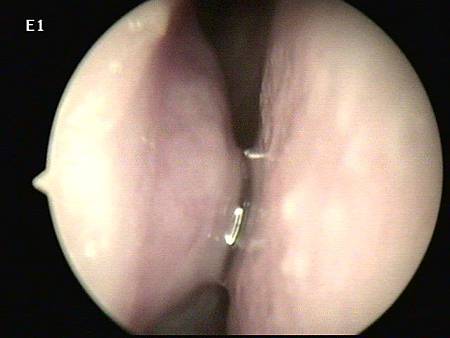

不用多說, 把內視鏡放進鼻子裡一看,

連她自己也嚇一跳!